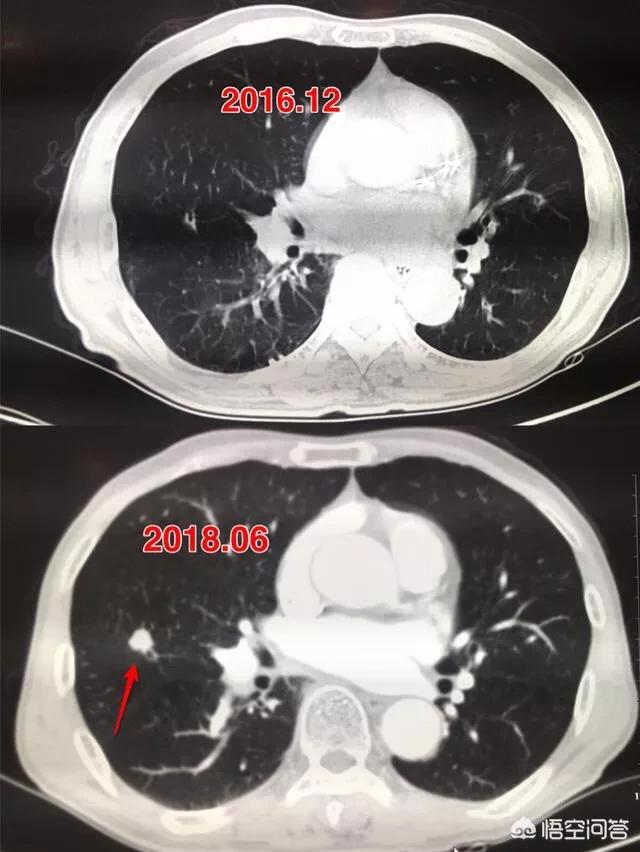

ちょうど2日前、私はある症例を読んだ。患者男性57歳、3年間の経過観察で、結節が0.5cmの大きさから肺がんになる過程を記録したばかりで、経過観察のたびに結節は大きくなっているが、患者は手術を選択しなかった。

矢印は結節を指しているが、2016年3月に発見されたときは約0.5cmと非常に小さかったが、今では定期検診でこのように非常に多くの結節が見つかっている。画像で良性か悪性かを判断する方法はなく、検討するという選択肢しかなく、検討と経過観察も最良の手段である。

7ヵ月後、2016年10月の2回目の経過観察では、この結節がより大きく、丸みを帯びていることが明らかになった。経過観察時の結節の拡大は悪性腫瘍の可能性を警告するものであったが、この患者はそれでも手術を選択しなかった。

さらに1年2カ月後、2017年12月に3回目の検査を受けた。この結節は以前よりずっと大きくなっており、悪性の徴候が小葉状に広がり、内部が固くなっているのがわかる。これらの徴候から、基本的に肺がんと診断されたが、それでも患者は手術を受けなかった。